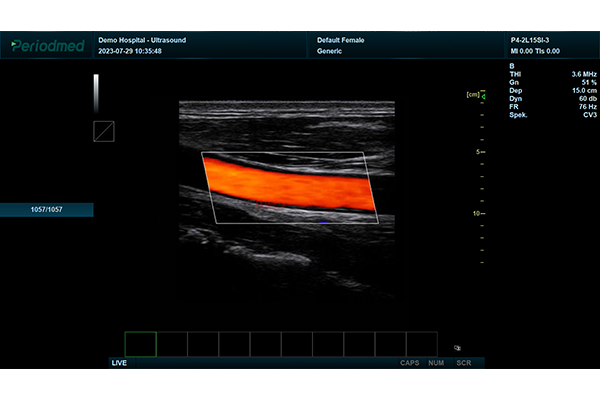

超声不仅对病灶部位大小、形态等特征的描述,而且通过彩色多普勒血流显像、能量多普勒血流显像和声学造影技术,观察脏器的血流灌注状态。肿瘤血流的灌入和流出状态,显示病变的血供和代谢状态,为疾病的诊断提供更丰富的信息,以造影剂为载体还可以将某些药物或抗体携带到靶区,依靠超声在局部的照射、微泡破裂释放药物或抗原抗体反应,出现靶区组织的回声改变,以达到诊断和治疗的目的。